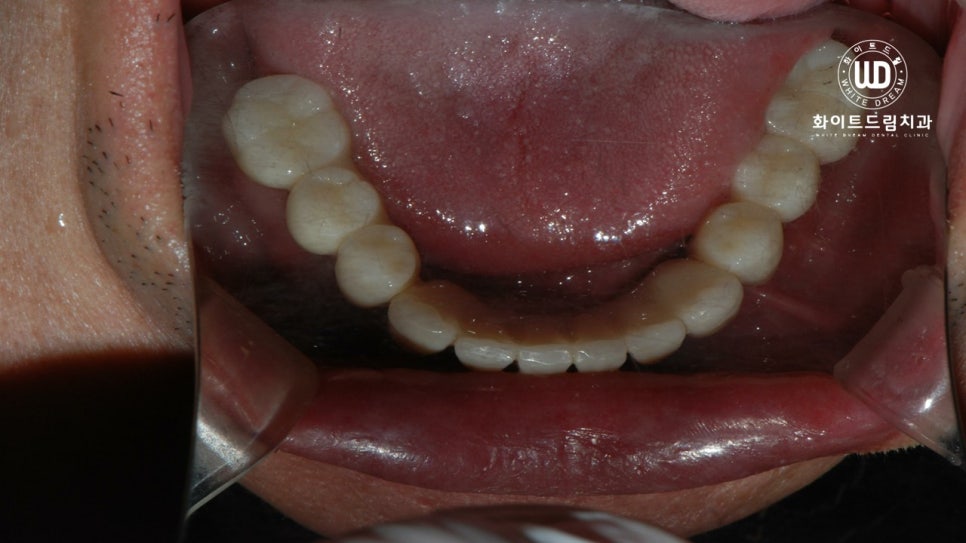

마지막으로, 하악 잔존 치아 2개 발치 후, 상하 전체 치조골 이식을 동반한 임플란트 식립 후 최종 진단 결과물입니다.

심미적, 기능적으로 주변 치아와 자연스럽게, 그리고 나이에 어울리도록 임플란트 시술이 마무리 된 것을 확인할 수 있었습니다.

뼈이식과 임플란트 식립에 있어서 가장 중요한 포인트는 바로 고정력 입니다. 임플란트를 여러개 식립하여 보철치료를 진행할 때, 저작하는 위치가 변하지 않고 모든 치아가 긴밀하게 위치할 수 있도록 교합 조절을 해드리는 것이 중요합니다.